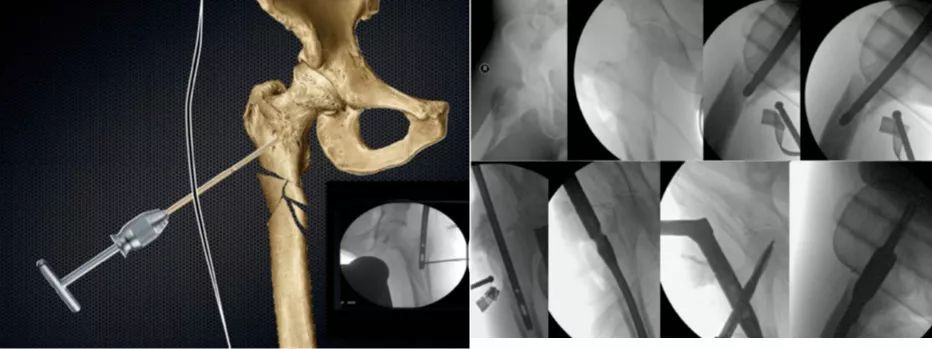

专题教程:青壮年股骨转子下骨折的髓内钉复位与进针要点

图片尺寸439x324